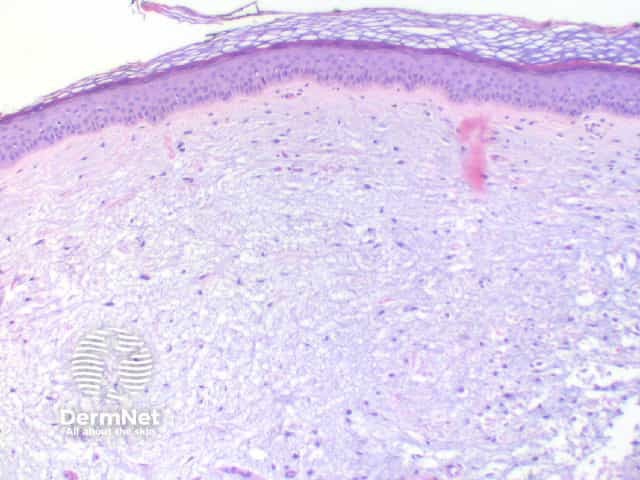

Lesions of focal mucinosis present with a dome-shaped elevation of the skin and a circumscribed dermal pool of mucin (figures 1, 2). Involvement of the subcutaneous tissue is uncommon. A delicate infiltrate of fibroblasts and an increase in capillary vessels can be seen within the lesion (figures 3, 4).

The mucin stains with colloidal iron (blue-green), and Alcian blue at pH 2.5 (blue) (figure 5).